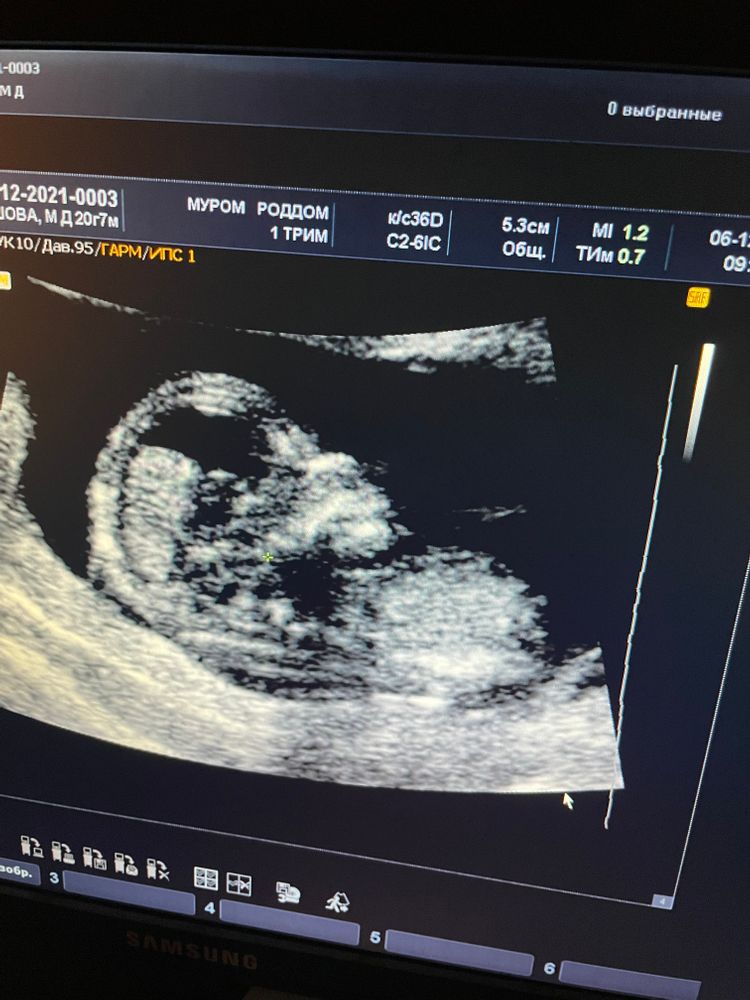

И вот лежу я на кушетке, на живот кладут датчик, пока ничего не смотрят, но человек на экране уже есть, а я.. Смотрю глазами по 5 копеек в потолок и боюсь перевести взгляд на экранчик - не дай бог увидеть там кириветку, которая давно не растёт. Спустя пару секунд заставила себя посмотреть и увидела человека! Так, человек это уже хорошо, но почему голова такая маленькая?? Неужели остановился недель в 11?!

Тут датчиком начинают давить на живот и тихонько водить им, а человек дергает руками и ногами, будто отмахиваясь от этого давления 🥳 понимаю, что человек развивается, сердце бьется, а это уже хорошо!

Смотрели меня долго, все показывали и рассказывали, сказали в заключение, что по всем моментам, которые можно посмотреть на этом сроке, у нас все отлично! Я очень счастлива 🤍

Человек, видимо, пошёл в меня: когда надо было посмотреть позвоночник, он лежал в профиль, и мне потрясли живот, чтобы он перевернулся. Перевернулся он секунды на 2, потом лёг обратно в профиль и начал барабанить ногами по стенке матки 🤣 затем стал отталкиваться и кататься на спине, выражая протест, что его побеспокоили. Но самое крутое, что после этого он повернулся обратно к нам спиной, обиделся что ли. Девочки, я ржала до слез 😂 Даже узистка улыбнулась с этой картины. Пока его не трогали - лежал спокойно, а как немного надавили, то сразу возмущаться. Вот я такая же, в целом молчу, но если не понравится как со мной обращаются, сразу наору, предупреждать не буду))

Мальчик или девочка? Очень хотели, чтобы пол написали на листочке и заказать пироженки, узнать дома с мужем, разделить эмоции. Но я не успела даже предупредить, чтобы мне не говорили пол. Все увидела, когда ещё даже бёдра не начали смотреть. Очень нестеснительный парень у нас 😂😂 Показал все со всех ракурсов, сказали: «Ну обычно мы можем предположить пол на таком сроке, а точнее говорят на 20 неделе, но у вас точно мальчик». Знаете, у некоторых девочек тут видела фотки, где правда пол непонятен: то ли это пуповина, то ли половой бугорок, то ли что.. Ну наш решил, что смущаться ему нечего, если есть что показать 😃